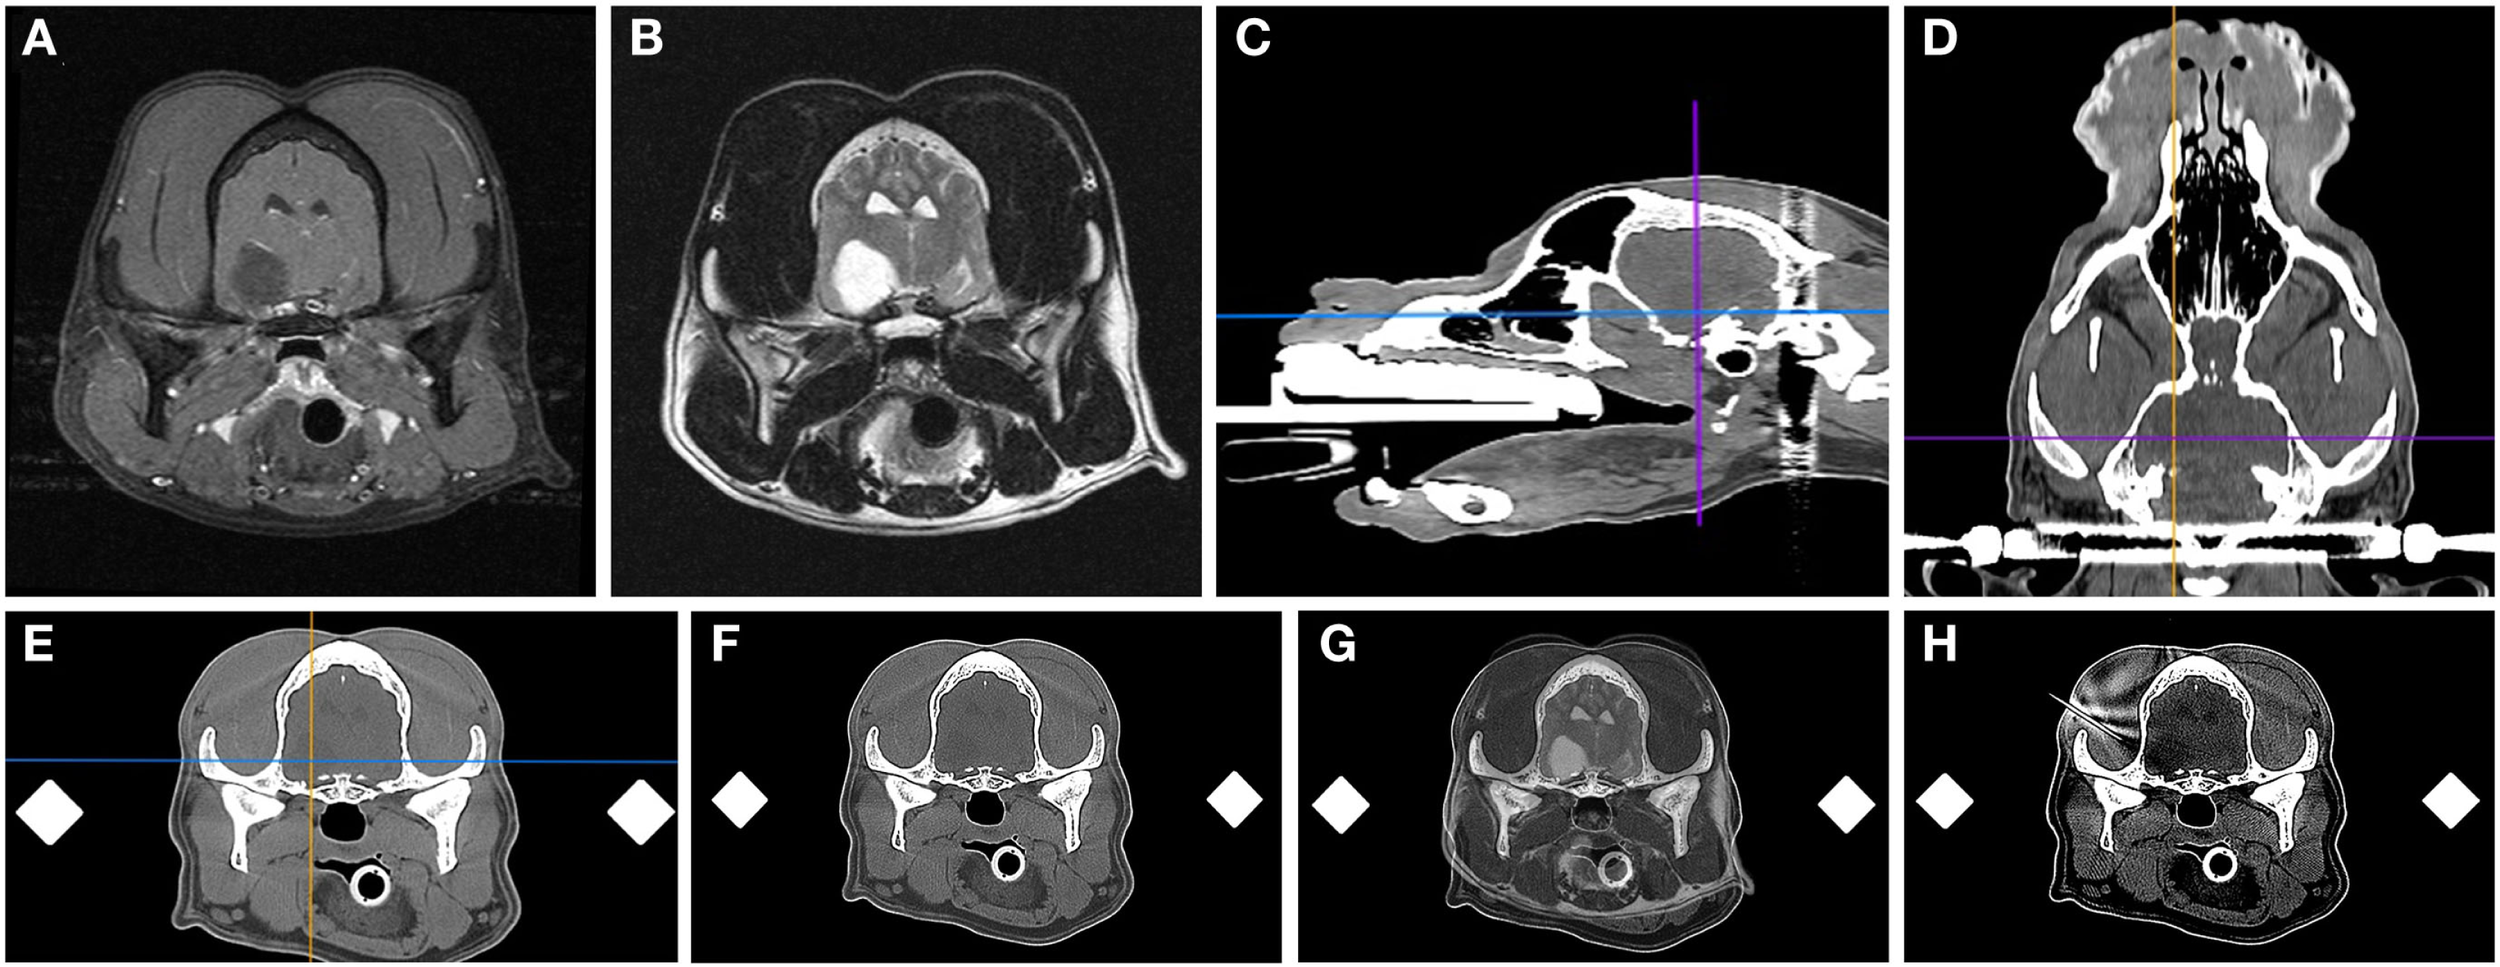

Figure 2

Frame-based stereotactic biopsy planning procedure from a dog with a Grade II astrocytoma. Diagnostic, transverse post-contrast T1-weighted (A) and T2-weighted (B) images demonstrating intra-axial, non-enhancing mass lesion in the right piriform lobe. The patient is anesthetized, immobilized in the headframe, and CT images obtained for stereotactic planning (C–F), imported into image analysis software (C–F) and co-registered with the prior diagnostic MR (G). The planned trajectory is then simulated and verified using a needle blank (H) and the final stereotactic coordinates recorded.

Stereotactic imaging and planning

DICOM formatted images of the stereotactic CT and diagnostic MR were imported into image analysis software packages (OsiriXMD and Mimics v.14.1, Materialise, Leuven, Belgium), co-registered, and the stereotactic coordinates and trajectories for lesion biopsy determined by a single investigator (John Henry Rossmeisl; Figure 2). The rostrocaudal coordinates were determined based on linear (ear bar) reference markers. Mediolateral and dorsoventral coordinates and/or angular trajectories were measured directly from DICOM images using osseous anatomic landmarks, including the external sagittal crest and external surface of the skull. Generally, the needle entry point and biopsy trajectory were planned to traverse the shortest distance of normal brain between the skull and the target, and avoid sulci, major vasculature, and ventricular structures. However, in some cases in which catheter- or electrode-based therapeutic interventions were to be performed following biopsy, the biopsy trajectory deviated from these criteria such that both the diagnostic biopsy and therapeutic procedure could be performed through a single craniectomy defect (26, 27). After the trajectory was planned, the manipulator arm was attached to the headframe and the biopsy trajectory simulated using a 20-gauge needle blank (Quincke Needle, BD Medical, Franklin Lakes, NJ, USA) that was positioned at the desired needle entry point into the calvarium. The CT scan was then repeated to include the headframe and attached needle phantom using contiguous 1 mm slices using the identical field of view and magnification factors as the initial scan for each patient (Figure 2H). The target depth was measured from the external surface of the craniectomy defect to the measured position of the mid-portion of the side-cutting port of the needle within the lesion. The final stereotactic (x, y, and z) coordinates obtained from the phantom scan were stored in the planning software and registered to the headframe.